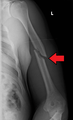

A displaced supracondylar fracture